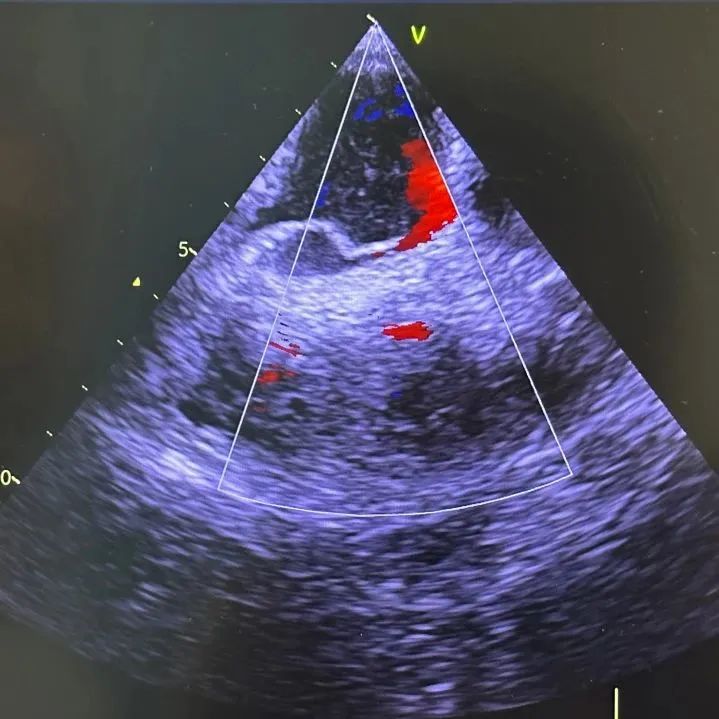

最终,右心声学造影等检查证实存在卵圆孔未闭,即心脏上多长了一个「孔」。

充分术前准备后,耿召华教授、超声科谭开彬教授同台为童爷爷开展手术。

术中,超声探头进入食管,从心脏后方向前近距离探查,进一步发现该卵圆孔未闭为复杂型,手术难较大。其腔道较长,约 24 毫米(一般为 4-18 毫米),且因相邻结构特殊,血液更易反流。

食道超声实时监测下,耿召华教授精细操作,经股静脉穿刺顺利送入导丝,由导丝引导送入尺寸最大的封闭器(25-35 毫米),通过卵圆孔后,逐一释放两侧封堵伞,直至固定良好,无残余分流,手术顺利完成。